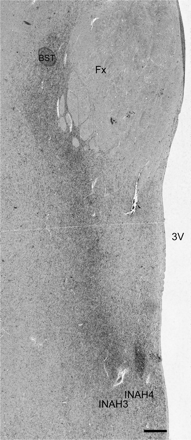

Following the autopsy, the hypothalamic region of the brain was fixed in 4% formaldehyde (pH 7.2) for 1–2 months (Tables 1–3) at room temperature and then dehydrated and embedded in paraffin. Coronal sections of 6 µm were then serially cut on a Leitz microtome (Leitz, Wetzlar, Germany). At a distance of every 15th section, three sections were selected for thionin and immunocytochemical stainings, stretched and mounted on SuperFrost/Plus (Menzel, Germany) slides, and subsequently dried overnight on a hot plate at 58°C. The region of the uncinate nucleus in the preoptic area was determined microscopically by the use of the human brain atlas (Mai et al., 2004) and the localization was confirmed by immunocytochemistry. Thionin-stained sections (12 ± 3 sections per patient) were obtained at regular distances, approximately every 90 µm, over more than the entire length of the uncinate for length determination. Subsequently, sections adjacent to the thionin-stained sections were immunocytochemically stained for NPY (anti-NPY) and synaptophysin (anti-SYN) (Fig. 1) as described later.

Representative photomicrographs depicting the uncinate nucleus in a thionin (A), NPY (B) or SYN (C) staining. NBB (Netherlands Brain Bank) # 98169, man 49 years old, INAH3 and 4: interstitial nuclei of the anterior hypothalamus 3 and 4, 3V: third ventricle. Scale bar = 500 µm. The insert in (A) is indicating the INAH3 and INAH4 subdivisions (shown by dotted line) that are characterized by a denser NPY and SYN innervation in (B) and (C). Scale bar = 63 μm.